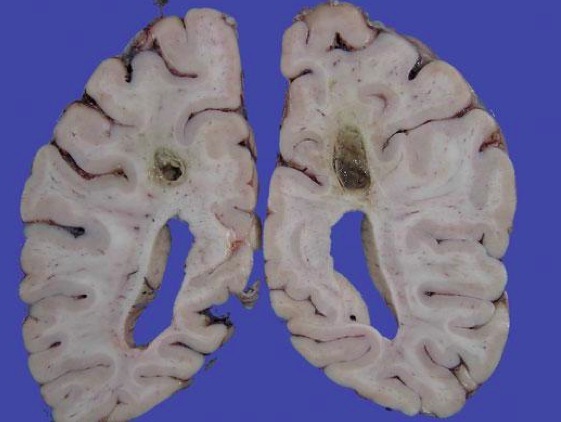

Brian abscess

Etiology:

Sx: ICP: Cushing triad (lower heart rate, mental changes, irregular breathing), papilledema, projectile vomitting, headache, fever

Dx: